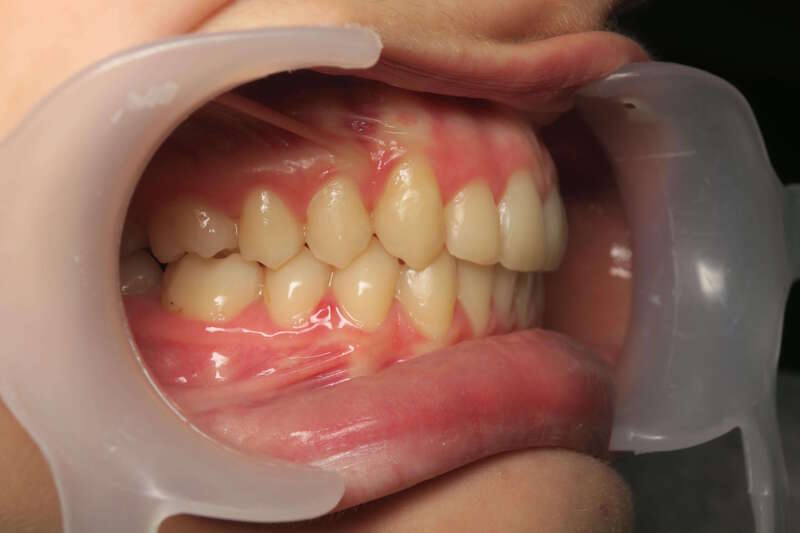

Cas n°1 d'orthodontie chirurgicale par aligneurs - adulte

Voici l'analyse de ce cas clinique concernant un patient adulte de 30 ans, illustrant la réussite d'un protocole ortho-chirurgical mené avec des aligneurs. Ce cas met en lumière l'importance de la fonction musculaire et respiratoire au-delà de l'alignement dentaire.

À 30 ans, la croissance est terminée, ce qui rend la correction d'un décalage osseux uniquement possible par la chirurgie :

• Rétrognathie Mandibulaire (Profil Rétrusif) : Le patient présentait un menton fuyant, caractéristique d'une mandibule trop courte ou positionnée trop en arrière.

• Déficit Fonctionnel : L'absence d'engrènement correct entraînait une mastication inefficace. Le patient rapportait une sensation de "manque de force" lors de l'alimentation.

• Supraclusion et Décalage : Un recouvrement incisif important qui bloquait toute dynamique mandibulaire saine.

• Usure et Fatigue : Chez l'adulte, ces malpositions entraînent souvent des tensions musculaires et une usure prématurée du capital dentaire.Le traitement a combiné la précision numérique des aligneurs et la puissance de la chirurgie maxillo-faciale :

1. Préparation par Aligneurs : Les arcades ont été préparées (alignement et coordination) pour que, une fois la mâchoire avancée par le chirurgien, les dents s'emboîtent immédiatement.

2. Avancée Mandibulaire Chirurgicale : Le repositionnement osseux a permis de corriger le profil de manière spectaculaire, redonnant de la force et de la structure au bas du visage.

3. Réhabilitation de la Force Masticatrice : C'est le point clé du ressenti patient. En retrouvant un engrènement de Classe I, les muscles masticateurs travaillent enfin avec un rendement optimal. Le patient ressent physiquement ce retour de puissance musculaire.

4. Harmonie du Profil : L'avancée du menton a équilibré les proportions du visage, offrant un profil plus affirmé et une meilleure définition de la ligne mandibulaire.

Avant

Après